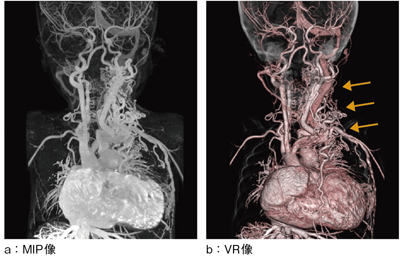

●症例2:頸胸部血管異常(図5)

2歳の患児に,頸胸部の異常血管走行の把握目的でCTAを施行した。頸椎や鎖骨に異常血管が複雑に入り組んでいるが(図5 b←),自動サブトラクションによって,技師が処理することなく骨が除去されたVR・MIP像を瞬時に得ることができた。これにより,検査直後の術前カンファレンスに画像を提供でき,手術方針が決定された。

図5 症例2:頸胸部血管異常